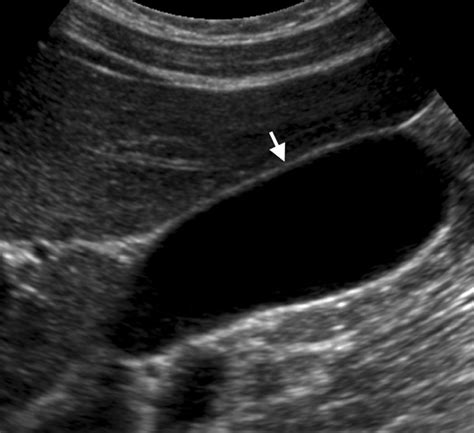

In clinical practice, the standard threshold used to define a normal gallbladder wall thickness is 3 millimeters (mm) or less. When a patient undergoes an ultrasound—the gold standard for evaluating this organ—the radiologist measures the wall when the gallbladder is in a distended state (filled with bile). If the wall appears thicker than 3 mm, it is clinically described as "gallbladder wall thickening."

It is important to understand that while 3 mm is the widely accepted cutoff, individual physiological variations exist. However, a thickness consistently exceeding this limit often triggers further clinical investigation to determine the underlying cause. Measuring the wall accurately is crucial because an thickened wall is often the first visual evidence of cholecystitis (inflammation) or other underlying pathologies.

Ultrasound is the preferred method for measuring gallbladder wall thickness due to its accessibility, safety (no radiation), and high sensitivity for detecting abnormalities. When a technician performs the scan, they look for specific criteria to ensure the measurement is valid.

• Distension: The measurement is most accurate when the gallbladder is full. A collapsed or partially filled gallbladder can create a false appearance of thickening.

• Positioning: The measurement is typically taken at the anterior wall, perpendicular to the ultrasound beam, to avoid artificial elongation or distortion.